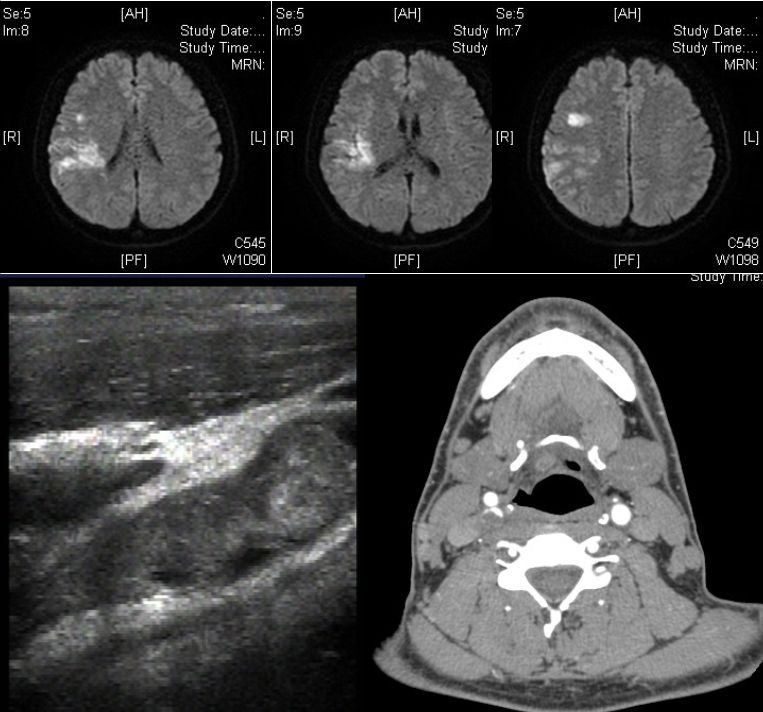

男性35岁。因头晕、左侧肢体无力半天入院。既往:发现血压偏高7-8年;嗜烟酒。查体:血压120/80mmHg,左侧偏瘫。实验室检查:红细胞 5.62*1012/L,Hb185g/L,抗磷脂抗体阴性。

答案:颈内动脉巨大漂浮血栓。颈动脉自由漂浮血栓(附着于血管壁的瘦长血栓,其远端大部仍有栓周血流)罕见,文献报道不超过150例。最常见的病因为动脉粥样硬化或溃疡斑块,也见于高凝状态、高纤维蛋白原血症、缺铁性贫血、血小板增多症、兴奋剂使用者。治疗以抗凝和稳定斑块为主。不常规考虑血管内治疗。因为:1)该血栓为延伸性,而非堵塞性;2)患者神经功能缺损相对轻;3)由于再发栓塞的风险很高,应当避免针对血栓的机械操作。若患者的临床症状恶化,应当进行紧急的机械取栓治疗(如抽吸血栓)。病情稳定后可行颈动脉内膜剥脱术。

病例2

患者,21岁女性,患者3小时前做某手术后突 发右侧肢体乏力、意识不清。

发病24小时磁共振:

答案:脑型脂肪栓塞综合征。患者做了自体脂肪填充术。脂肪栓塞综合征(fat embolism syndrom,FES)是指直径为10~40μm的血管内脂肪颗粒阻塞血管腔而引起的一系列病理生理改变的临床综合征。FES常发生于骨创伤及骨手术病人。FES潜伏期为6~24h,FES 的典型三联征为低氧血症、意识障碍和瘀斑。